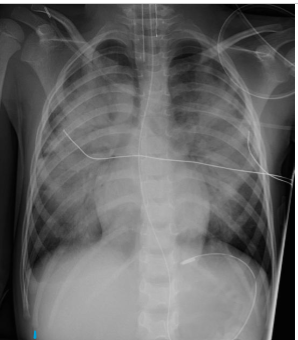

where is the endotracheal tube supposed to end and why

above the “carina” (bifurcation of the lungs)

If not, it tends to move when the pt flexes/extends neck and has a tendency to slip into the R mainstem bronchus. This leads to only ONE lung getting air and may lead to collapse of the other (u will not hear the other lung when u auscultate)

whats the dx

pneumonia (R side?)

consolidation, heterogenous opacity, localized